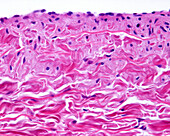

13613516 - Vein adventitia, light micrograph